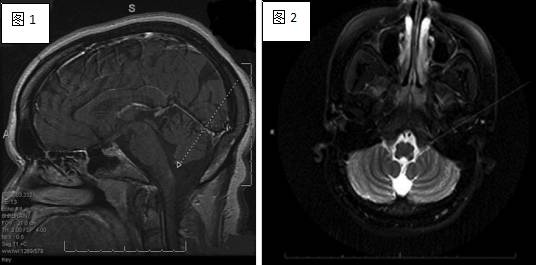

视神经脊髓炎病灶在Tl上常为等或稍低信号,T2及常表现为高信号。特征性病灶位于下丘脑、丘脑、三脑室、导水管、桥脑被盖及四脑室周围。神经脊髓磁共振成像通常显示多个脊髓节段受累,急性期常见脊髓肿胀和明显实质性、环形或线性强化;相对严重的病例可出现髓内多个节段的空腔样坏死灶,更为严重者颈髓病变累及低位延髓,疾病晚期可出现脊髓萎缩。

T2及FLAIR序列延髓背侧和胼胝体压部病变区高信号